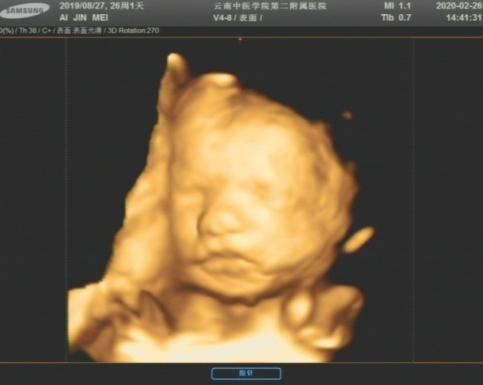

三星RS80A全身高端彩色多普勒超声诊断仪,可适用于胎儿、腹部、血管、心脏、小器官等多脏器项目检查,其中该诊断仪也是目前公认较为先进的妇产科超声诊断仪,具有极高的清晰度和分辨率,四维仿真成像,给人以真实的深度透视感觉,诊断仪同时配备了具有更宽频带和更高灵敏度及穿透力的高密度超宽频单晶体探头群,能很好的显示疾病的病变范围以及病变程度,有效避免疾病的漏诊和误诊。

(胎儿四维成像图) (肝脏结节超声与CT对比图像)